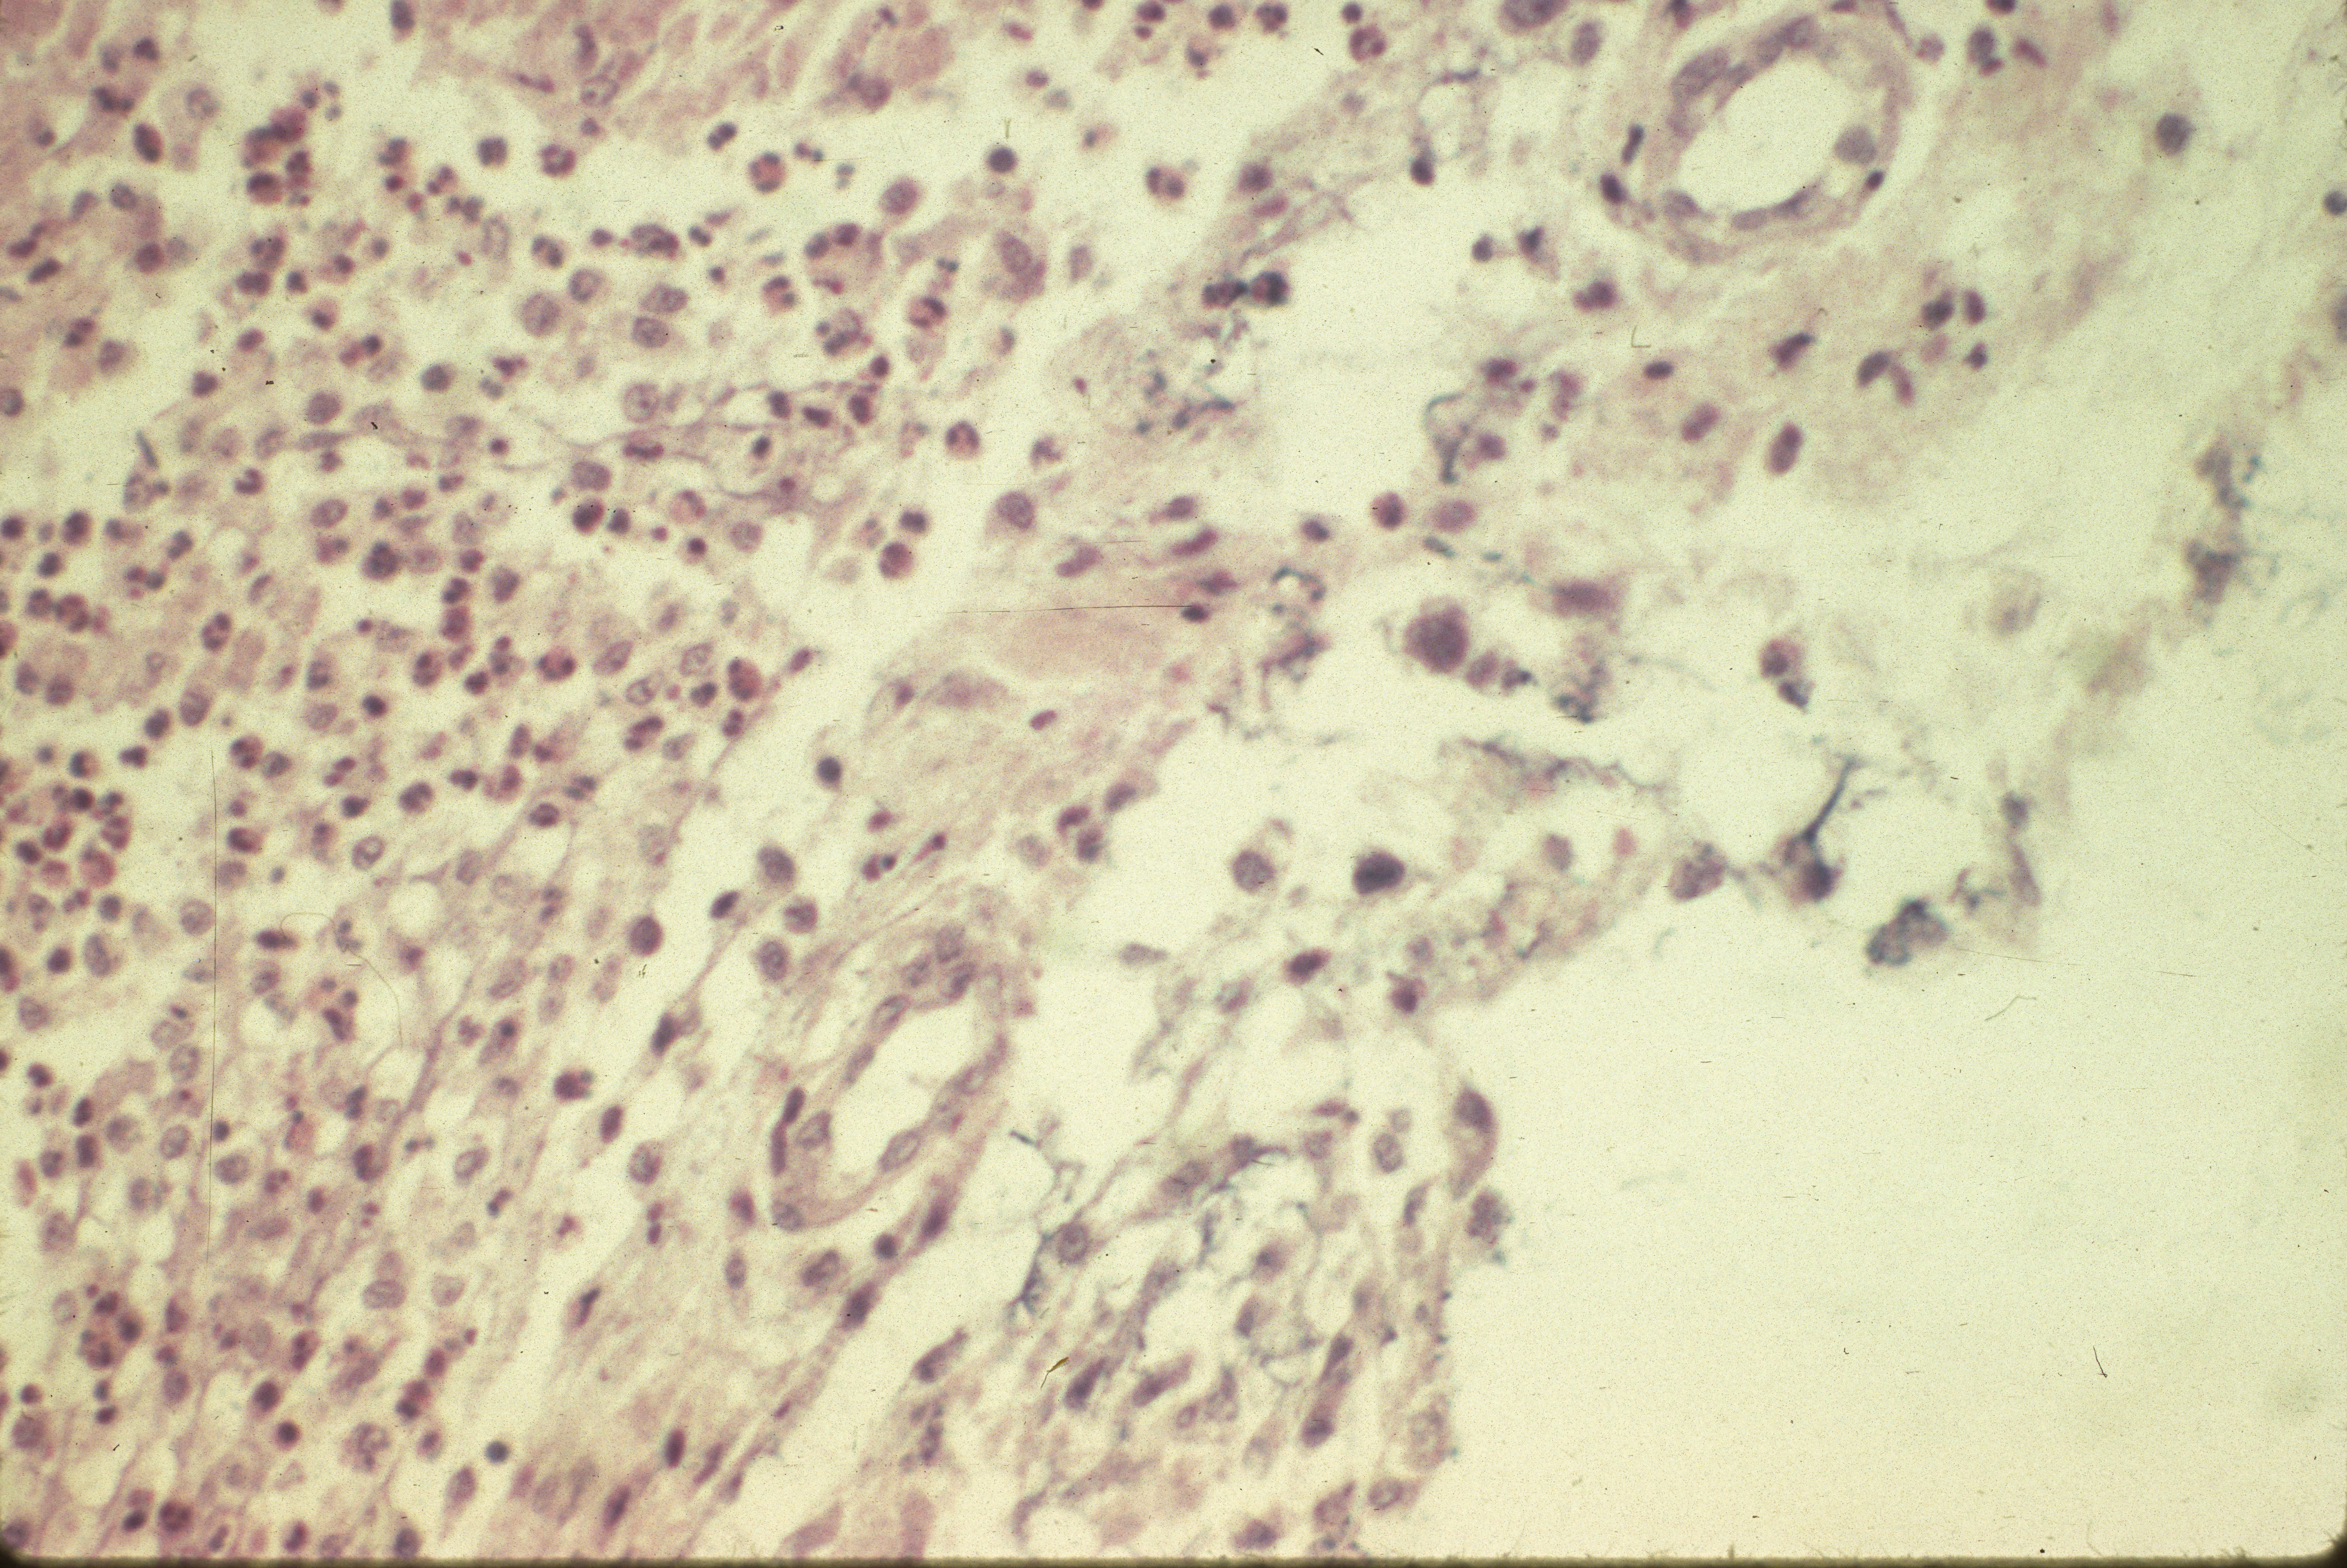

Mycoplasma synoviae infection (slide study set no. 12) Item Info

Mycoplasma synoviae infection (slide study set no. 12)

Slide study set #12, mycoplasma synoviae infection, 2 sets (includes 40 color slides), 1983